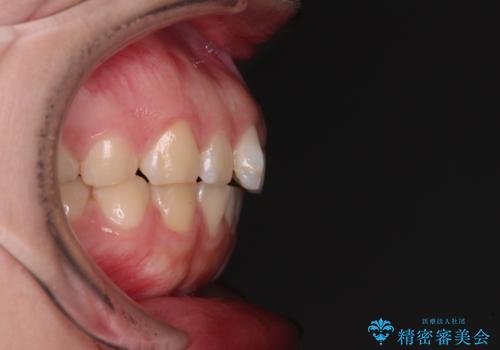

八重歯を短期間で改善 ワイヤー装置による抜歯矯正

- 著しい八重歯を気にして来院された患者様です。

片側の八重歯であり上顎の正中がずれていたため、上顎左右第一小臼歯2本を抜歯して排列することとしました。

下顎の骨格的なズレが大きかったため、上下歯列のバランスが取れるか心配でしたが、上下ともに左右対称に近い歯列で治療を終えることができました。